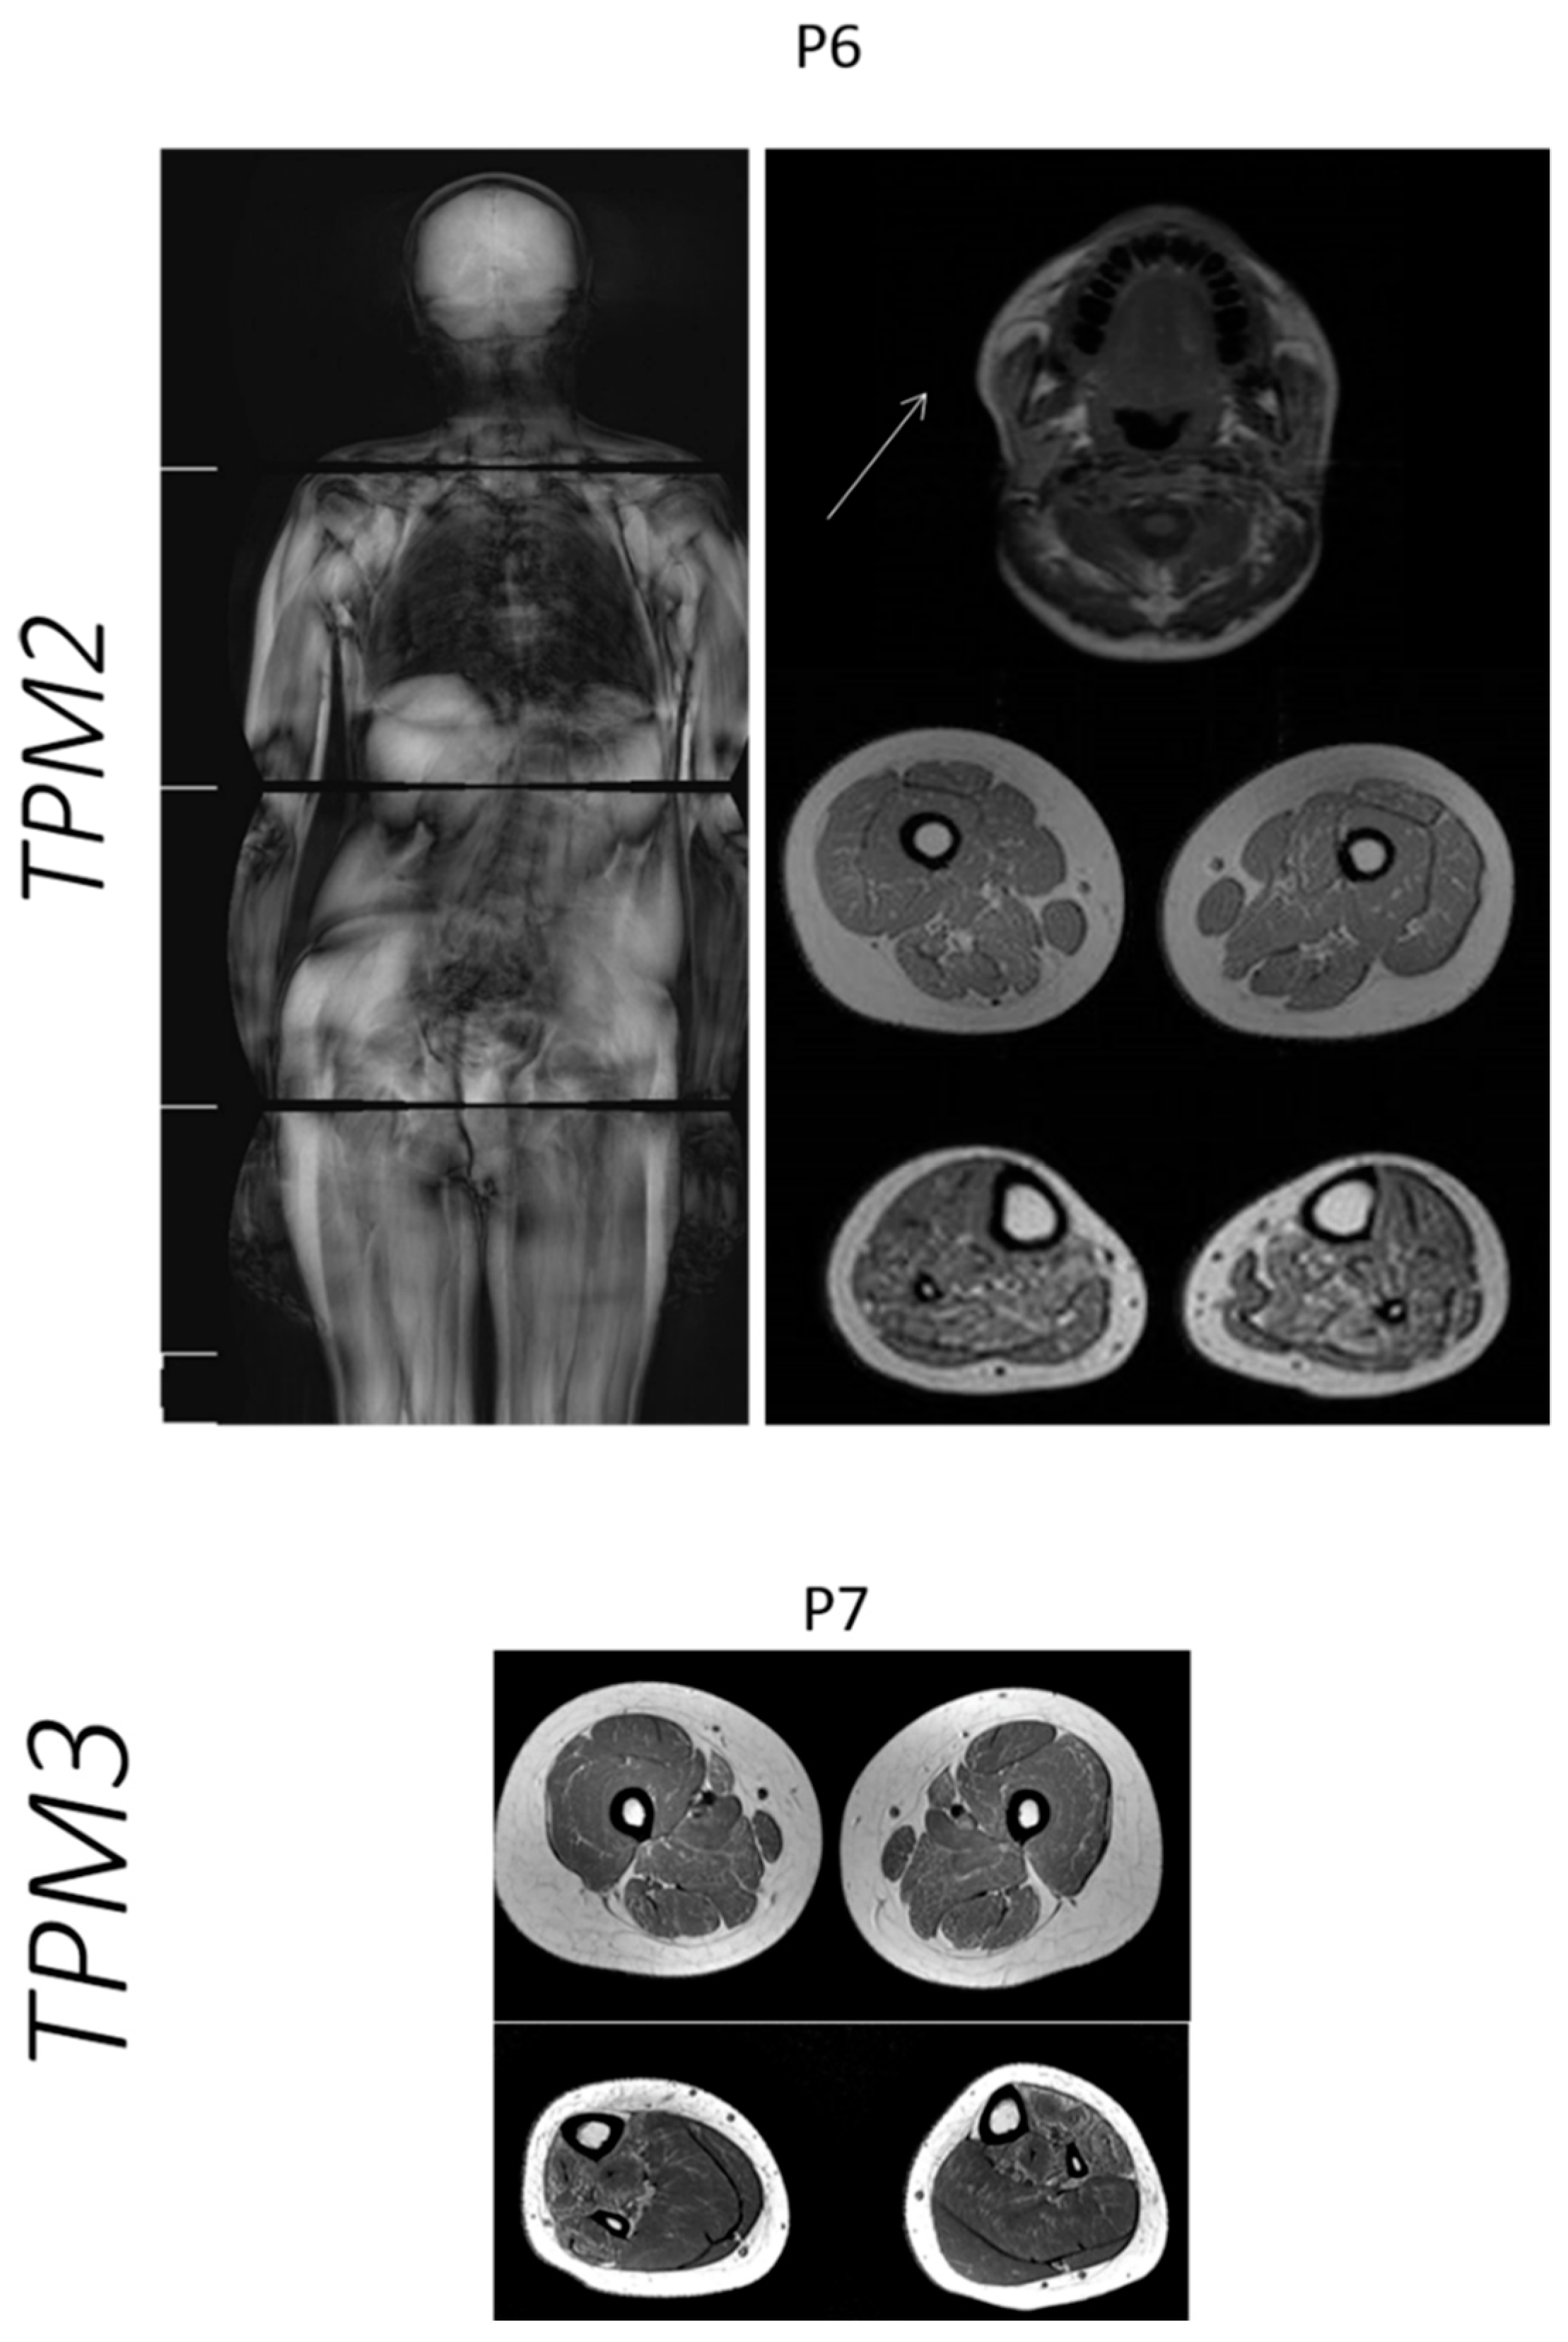

| Case | Age at Muscle MRI | Gene | Muscle MRI or CT (Mercuri Grade *) | |

|---|---|---|---|---|

| Thigh: | Legs: | |||

| P6 | 12 years | TPM2 | Vastus lateralis and rectus femoris muscles: grade I OBS: Axial T1 image of the head: Involvement of temporal, masseter and pterygoid lateral muscles: grade II | Soleus muscle: grade IIb Gastrocnemius muscle: grade IIa |

| P7 | 13 years | TPM3 | Sartorius muscle: grade IIb Adductor magnus muscle: grade IIa Hamstring muscles: grade I | Soleus muscles: grade I Gastrocnemius muscle: grade I Tibialis anterior muscle: grade IIb Tibialis posterior muscle: grade IIb |